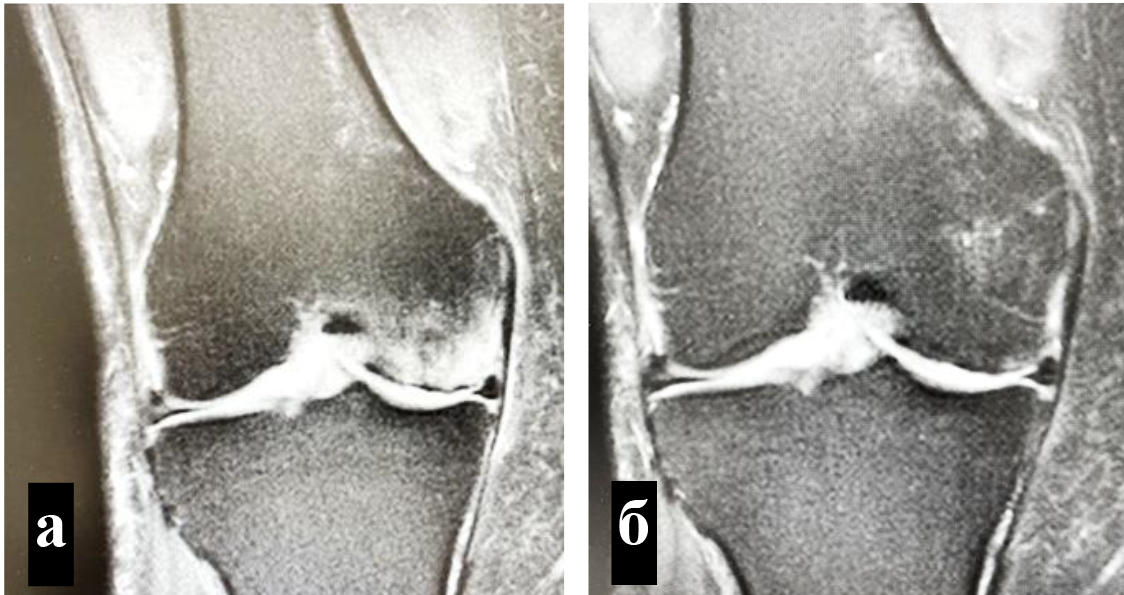

Для определения локализации и распространенности перегрузочного отека костного мозга всем пациентам выполняли МРТ. На Т1-взвешенных изображениях визуализировали снижение интенсивности сигнала, на Т2-взвешенных изображениях с жироподавлением и на коротких последовательностях «восстановления – инверсии» (STIR) выявляли высокую интенсивность сигнала (рис. 1).

Объективным показателем регресса болевого синдрома и нормализации клеточного метаболизма субхондральных структур являлось значительное сокращение объема или вовсе исчезновение зон трабекулярного отека костного мозга, что подтверждалось уменьшением гиперинтенсивных участков по данным МРТ (рис. 4) [8].